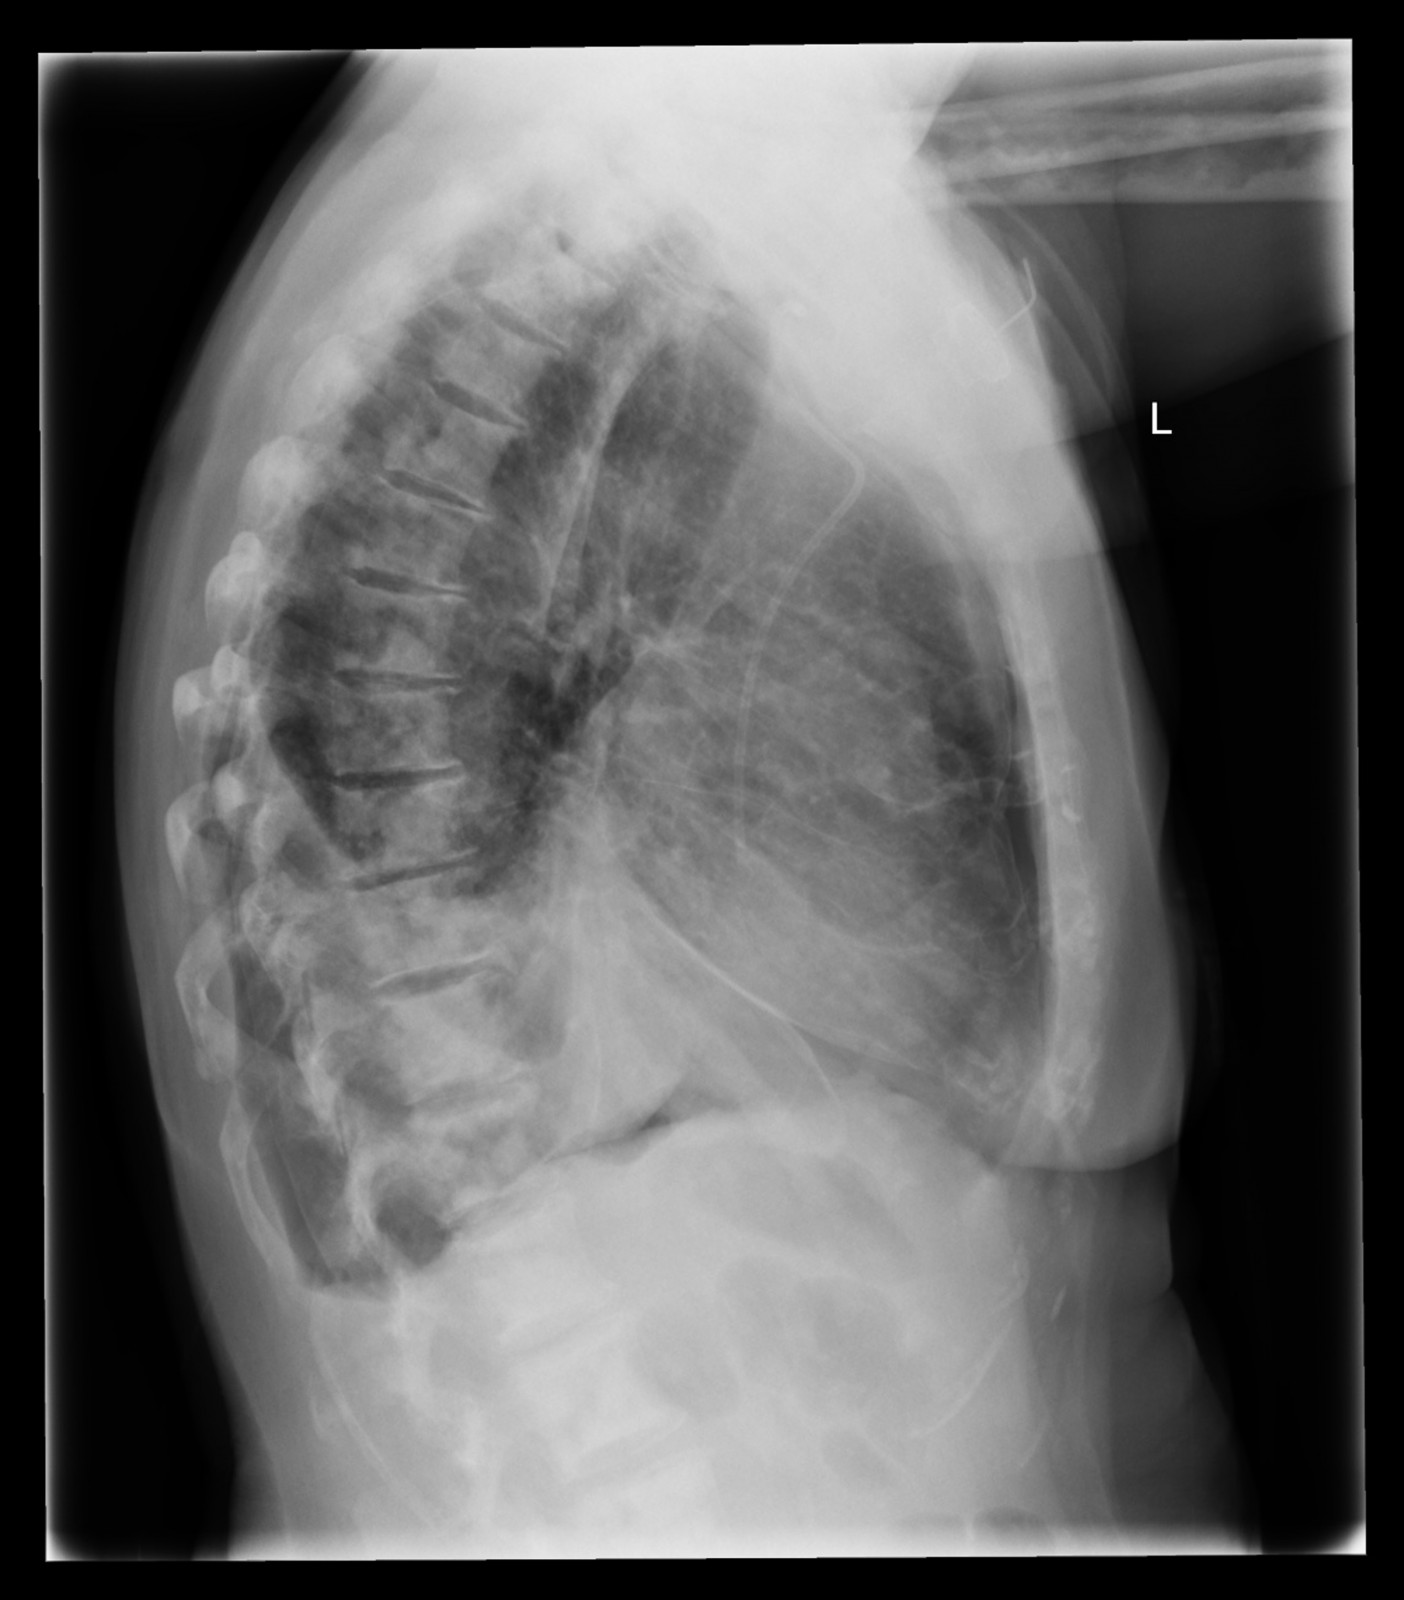

Röntgenfall des Monats Mai 2017 mit Auflösung

74 jährige Patientin mit diffusen Skelettschmerzen und akut aufgetretener Dyspnoe. Z.n. Mammakarzinom rechts.

seitlich

Bild vergrössern